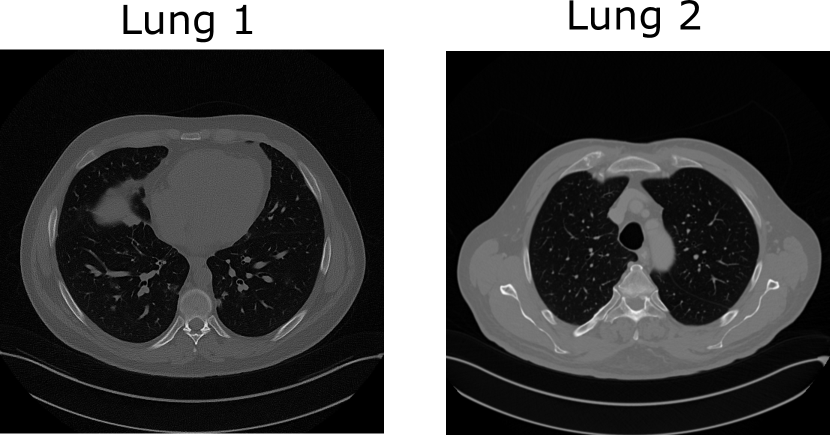

Refer to caption

Figure 3: The objects Lung 1 and Lung 2 with size 512×512512512512\times 512 from which noisy and incomplete X-ray projection data were generated. Both the objects are displayed in the grayscale range of [0,1]01[0,1].

V-B CT imaging system with limited angular range

Numerical studies were also performed with incomplete and noisy X-ray CT measurements from a stylized CT imaging system. The objective of these studies was to demonstrate the ability of the PULSE++ method to perform empirical sampling in higher-dimensional spaces (resolution 512×512512512512\times 512 pixels) in a computationally feasible manner. The CT-StyleGAN model introduced in Sec. III was employed for these studies to find alternate solutions from the same X-ray photon projection data. Two separate CT lung images of size 512×512512512512\times 512 pixels were selected from the NIH DeepLesion dataset to represent objects 𝐟𝐟\mathbf{f} from which measurement data were simulated. It should be noted that these images were not included during training of the StyleGAN. The objects, denoted as Lung 1 and Lung 2, are shown in Fig. 3. The maximum linear attenuation coefficient values in Lung 1 and Lung 2 were 0.063 mm-1 and 0.046 mm-1, respectively. The physical unit of each pixel (px) was 0.82 mm [42]. A fan-beam geometry with a linear detector array and a monoenergetic source was assumed. Projection data were simulated for 120 views spanning the limited angular range [0,119]superscript0superscript119[0^{\circ},119^{\circ}]. The noiseless X-ray measurements 𝐠¯M¯𝐠superscript𝑀\bar{\mathbf{g}}\in\mathbb{R}^{M} from an object 𝐟N𝐟superscript𝑁\mathbf{f}\in\mathbb{R}^{N} were modeled as [60]